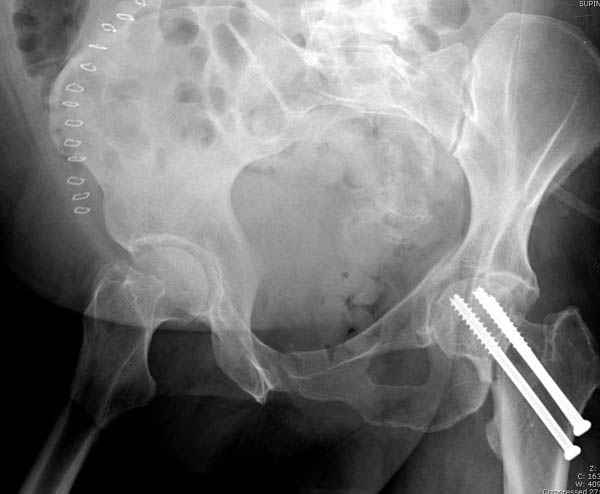

Уважаемые коллеги! С прошедшеми Вас праздниками. Теперь ближе к трудовым будням. Поступила 16 летняя девушка неделю назад. Механизм травмы падение с 5 этажа. Краткий диагноз:закрытый перелом левой ключицы, левого плеча, закрытый вертикально и ротационно нестабильный перелом костей таза:закрытый перелом левой подвздошной кости, переломы лонной кости справа, перелом обоих колонн вертлужной впадины слева;субкапитальный перелом шейки левой бедренной кости со смещением. По тактике лечения таза возникли следующие вопросы: 1. С чего начать - фиксации переломов вертлужной впадины или устранения деформаций таза? 2. Надо ли фиксировать шейку или фиксировать бедро в аппарате вместе с тазом, а после сращения таза планировать ТЭП ТБС? Если имеются еще какие подводные камни, будем рады выслушать.Спасибо.

У нас в таких случаях однозначно сделали бы остеосинтез Ш.Б. компрессирующими винтами, затем ЗВО таза, однозначно с дополнительной фиксацией в этом же аппарате бедра с разгрузкой тазобедренного сустава

Долгое ожидание повышает риск АВН головки,

рекомендуется ургентная фиксация шейки в первые сутки, а в дальнейшем таз.

В данный момент скелетное вытяжение поучается через перелом шейки, а фиксированный перелом шейки будет участвовать в процессе вытяжения через каннюлированные шурупы.

На снимке ацетабулума редко встречающийся очень низкий перелом, наверное, трудно было репозицию через один доступ? Перелом как бы замкнулся в квадрилатеральной поврехности.

В положении на спине подвздошным и надлобковым доступом восстанавливается тазовое кольцо, фиксация пластинами. При хорошей репозиции может улучшиться конгруэнтность в суставе.

Затем, если положение хорошее, закрытый остеосинтез шейки винтами.

Если нет - в положении на боку, синтез задней колонны из наружно-латерального доступа и синтез головки винтами, но уже под визуальным контролем.

На картинке подобный случай, только без шейки, сделано через месяц или полтора после травмы.